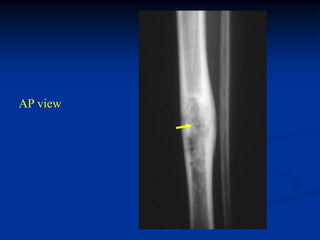

Case #1096

18 year male with

adamantinoma tibia

Axial T-2 MRI